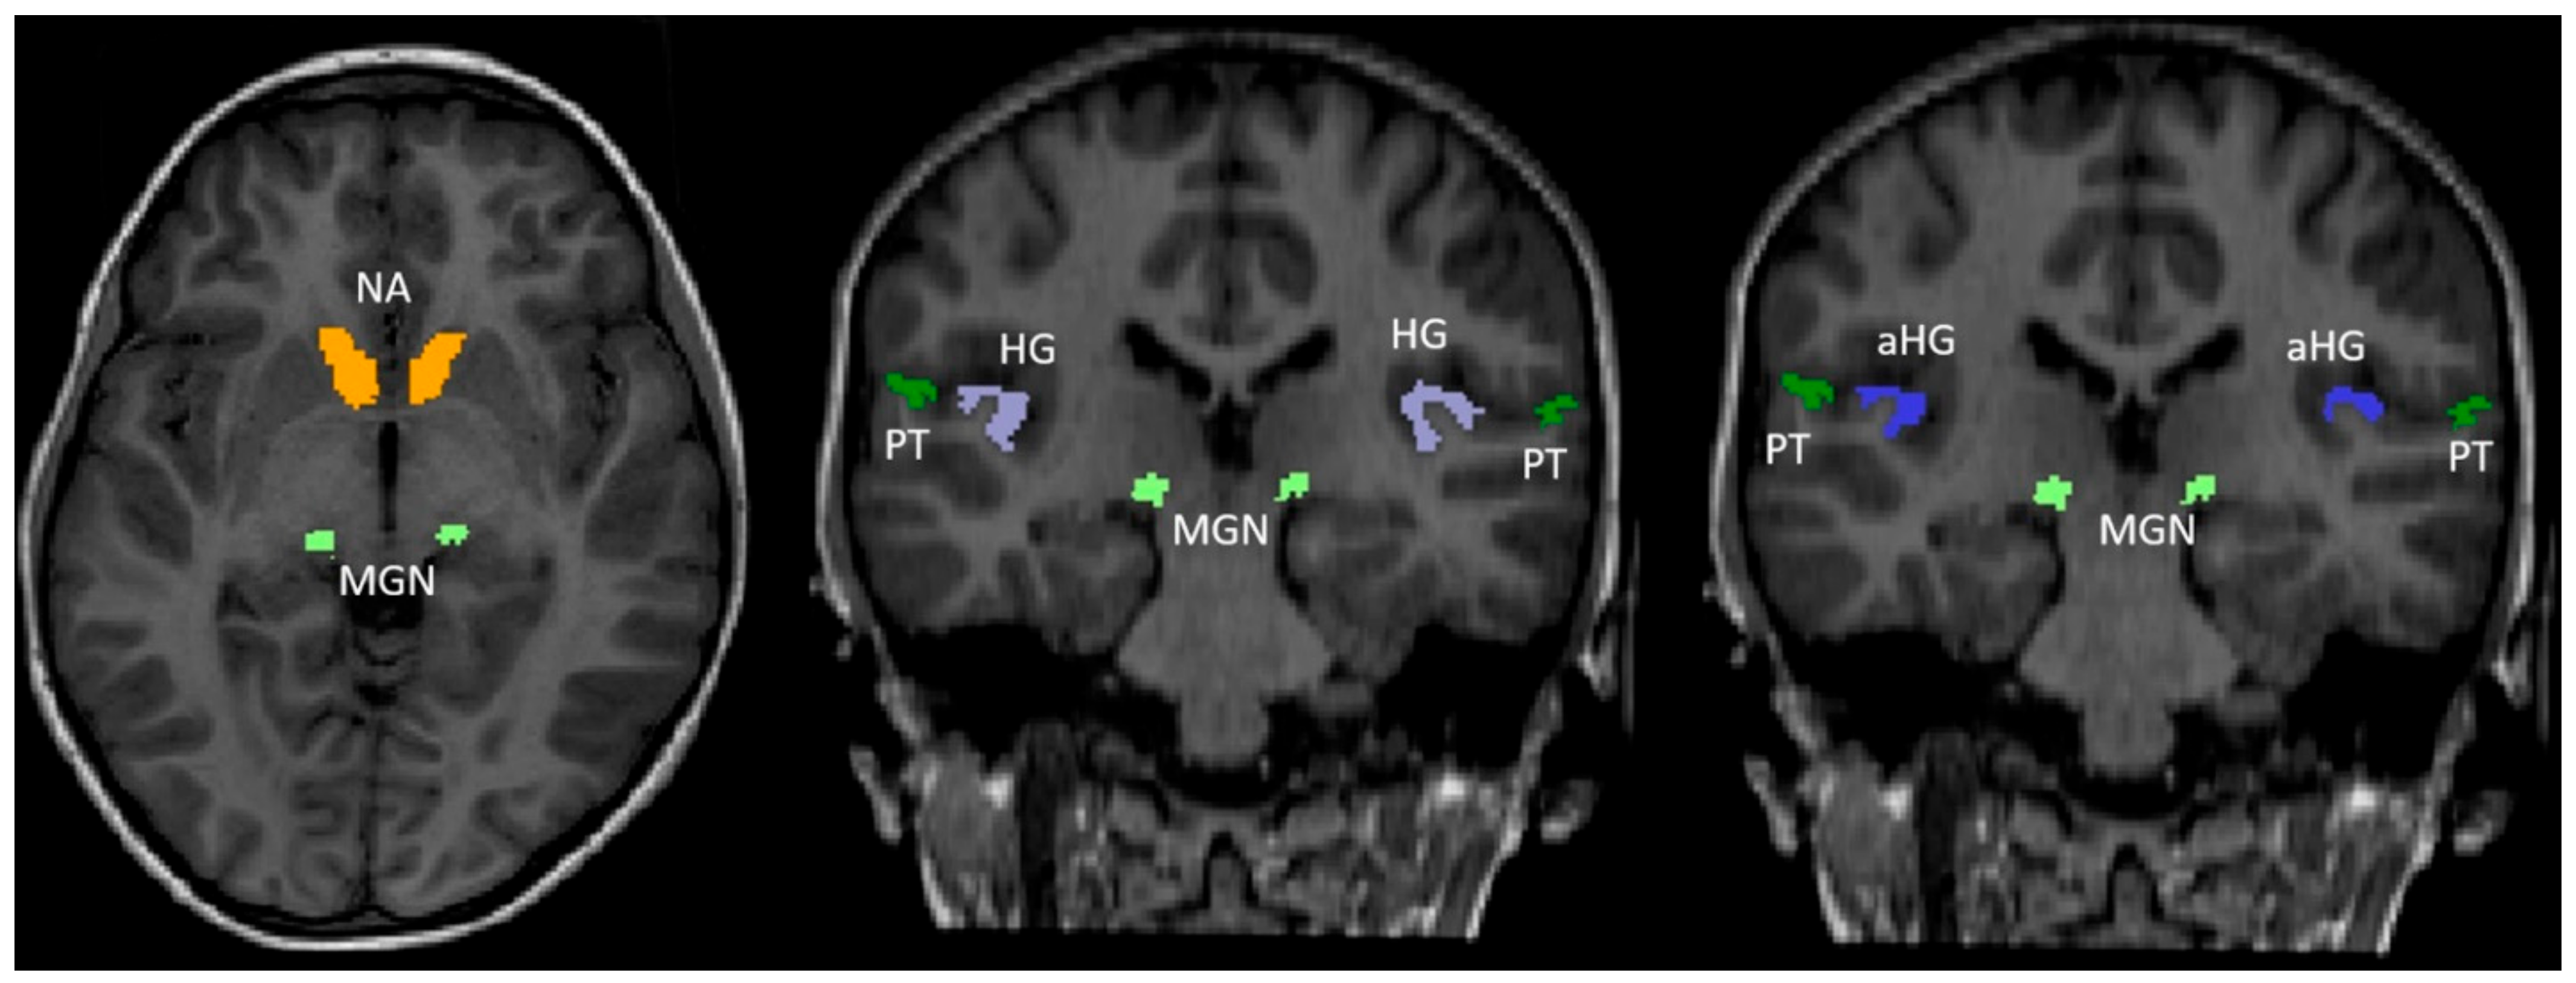

FreeSurfer is a widely used, open-access software package for structural brain imaging analysis [21,22,23]. It serves as an automatic reconstruction pipeline for the processing of brain images, including skull stripping, motion artifact correction, B1 bias field correction, gray–white matter segmentation, and region labeling on the cortical surface using different atlases in pediatric [24,25] and adult age groups [26,27,28]. Technical details are available from prior publications [29,30,31]. De-identified T1 structural examinations were made available from our local picture archiving and communication system (PACS) and processed using FreeSurfer version 7.1.1 (Massachusetts General Hospital, Harvard Medical School; http://surfer.nmr.mgh.harvard.edu (accessed on 1 September 2020)) [29], which aligns the input examination to the Desikan–Killiany [26], Destrieux [27], and Iglesias [32] atlases. Experience has shown that FreeSurfer has a high failure rate with data from patients younger than 1 year old. Zöllei et al. developed Infant FreeSurfer [24] to address this problem, incorporating age-matched templates to produce reliable automated brain segmentation in infants. However, infant FreeSurfer aligns the input examinations to the Desikan–Killiany [26] atlas only. To manage the processing, we wrote our in-house, web-based, data management software running on the FreeSurfer server (Lenovo Legion C730 with i9 processor and 32 Gb of RAM (Lenovo, Quarry Bay, Hong Kong)). The anatomical regions of interest (ROI) included the available regions of the brain involved in the auditory system, including the anterior HG (aHG), HG, PT, MGN, and NA. The aHG and PT were extracted from the Destrieux atlas (children aged 13 months to 18 years), while the HG and NA came from the Desikan–Killiany atlas (all study participants). The Iglesias atlas was used to extract the MGN (children aged 13 months to 18 years). Whole-brain volume was obtained from the Desikan–Killiany atlas for all study participants. The inferior colliculi are part of the central auditory system but were not assessed, since they are not included in the FreeSurfer atlases as a separate anatomical region. The parcellated output was displayed with the respective label map overlay and images were visually inspected for quality of regional segmentation results (Figure 1).

Figure 1.

Anatomical structures used in the FreeSurfer analysis overlaid on a coronal reformat of the T1-weighted sequence. Axial and two coronal reformat of the T1-weighted sequence show the color-coded hearing-related brain structures we studied: Heschl’s gyrus (HG, purple, anterior HG (aHG, blue), planum temporale (PT, dark green), medial geniculate nucleus (MGN, light green), and nucleus accumbens (NA, orange).